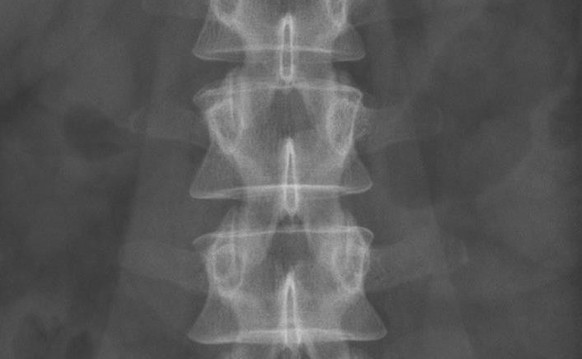

Dies, obwohl der Chirurg beratend bei der Entwicklung der Implantate dabei war und wusste, dass diese bei den Versuchs-Affen zu einer Erosion der angrenzenden Wirbel führten. Ausserdem bildete sich ein Ödem beidseits des Rückenmarkes und Flüssigkeit zwischen Knochen und Implantat. Dies deutet auf eine Entzündung oder eine Lockerung des Implantats hin.

29 Patienten erhielten trotzdem im Rahmen einer Studie ab 2009 ein solches Implantat der britischen Firma Ranier Technology. Zum wissenschaftlichen Beirat von Ranier gehörte auch der Schweizer Orthopäde Thomas Steffen, Professor an der Universität Zürich.

Im März 2014 wurden schliesslich alle diese Implantate mit dem Namen Cadisc-L zurückgerufen: Bei zwei Dritteln war es zu ernsthaften Problemen gekommen und die Betroffenen litten oder leiden teilweise immer noch unter starken Schmerzen.

Inzwischen musste bei sechs Patienten das Implantat entfernt werden, obwohl die Operation mit grossen Risiken verbunden ist. Bei weiteren fünf hat sich die künstliche Bandscheibe verschoben, bei neun Studienteilnehmern zeigt das Implantat Fehler, wie zum Beispiel Risse. Dies zeigt der «safety report» von Ranier, der den Journalisten vorlag.